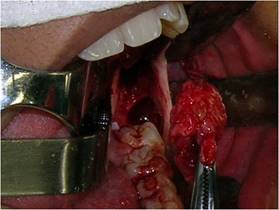

In sequence, a circumferential incision was made with a #3 scalpel handle equipped with a 15 blade, deep enough to penetrate the lesion. This tissue was removed, and a fragment of the lesion capsule was also removed separately to obtain a more specific lesion sample (Fig. 4).

Teeth 18, 28, and 48 were initially extracted by applying traditional surgical techniques. The remaining cyst was then addressed through an elliptical incision of approximately 0.5 cm from the opening of the decompression area. After total enucleation of the remaining cystic capsule and tooth 38 (Fig.7), the cavity was packed with medicated dressing as in the first intervention (Fig.8).